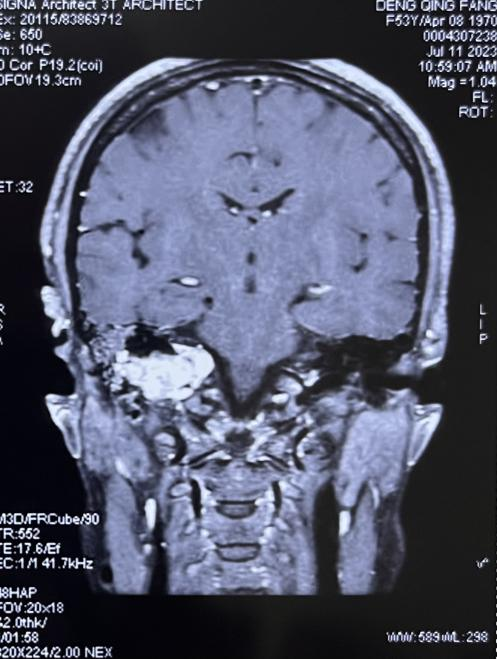

颈静脉孔区为侧颅底解剖最复杂的区域,该区域手术极其复杂,难度系数大,手术风险高。患者术前检查示右侧颈静脉孔可见不规则团块,等T1稍长T2信号影,大小约35mm*28mm*30mm,病变边界不清,内见多发迂曲血管,临近软脑膜可见明显强化(图1、2)。因肿瘤范围大,手术难度及并发症发生率极高,因此该患者入院后进行全面评估,并在耳鼻咽喉头颈外科主任任晓勇教授主持下,进行全院MDT讨论,麻醉科吴刚教授,神经外科许刚教授,以及全体耳鼻喉科医生进行疑难病例讨论。最终确定采用颞下窝typeA入路行肿瘤切除,并行外耳道封闭术。

图2